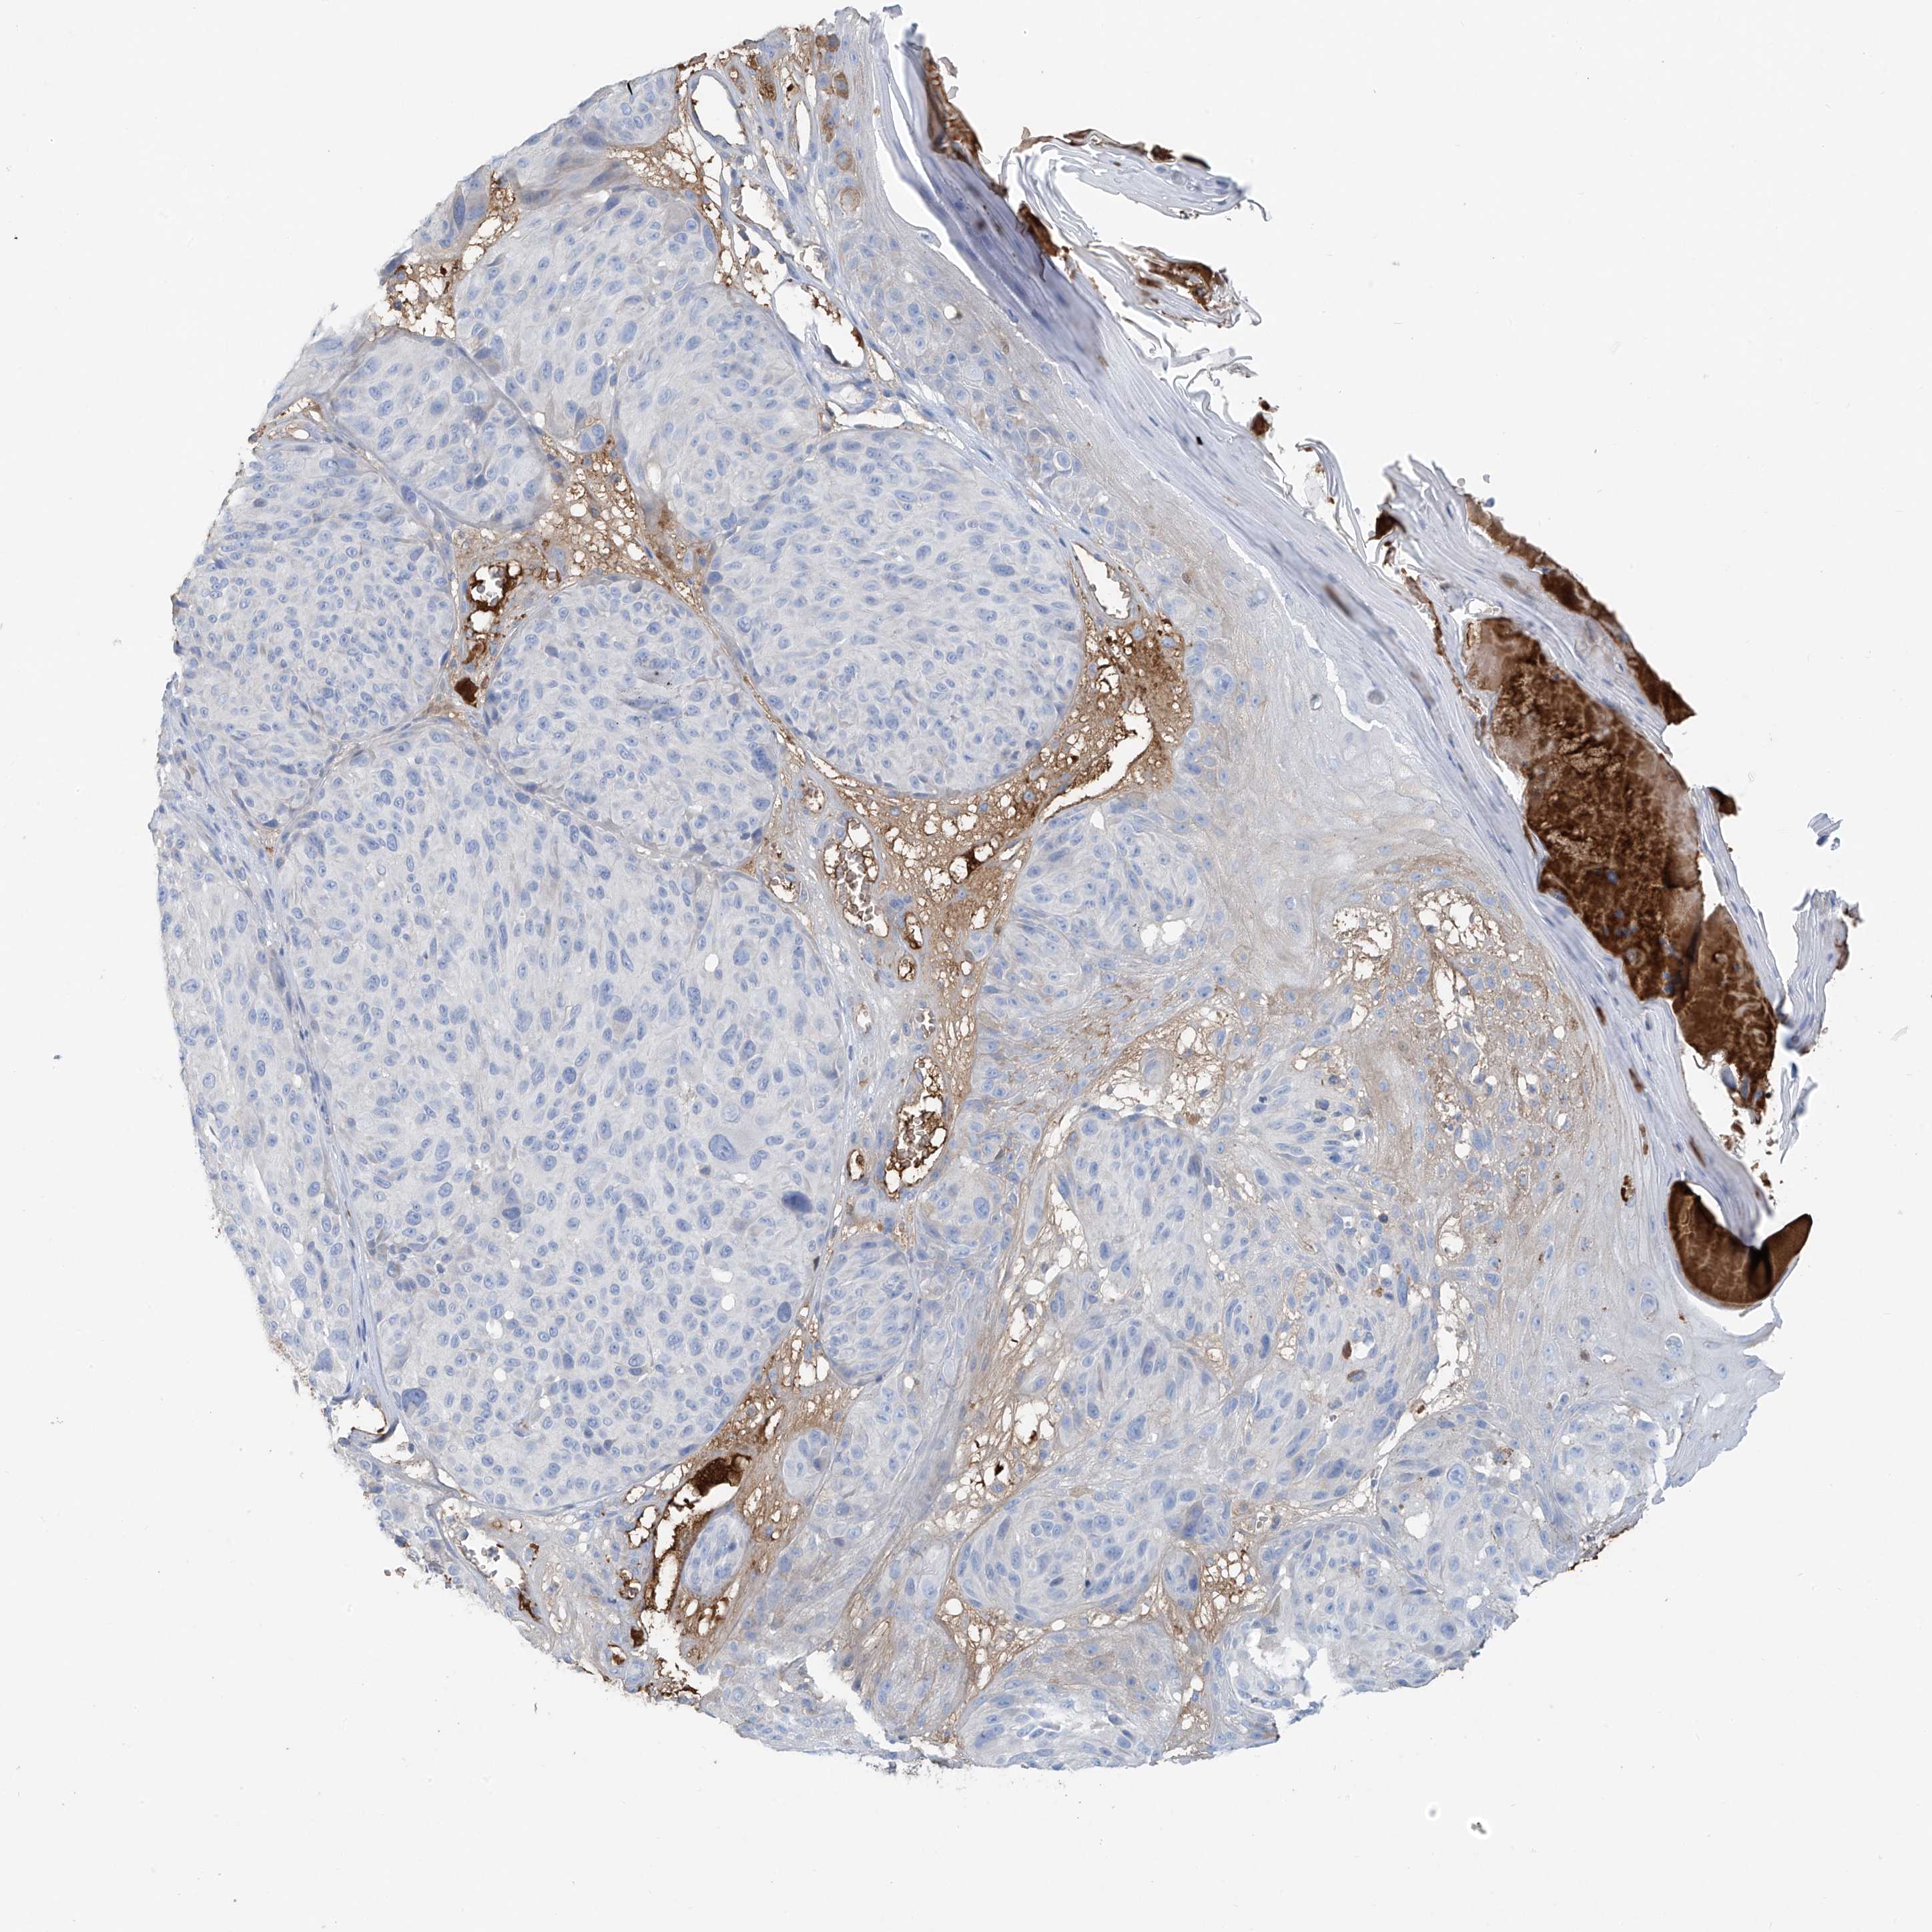

MELANOMA - Protein expressioni

A mouse-over function shows sample information and annotation data. Click on an image to view it in a full screen mode. Samples can be filtered based on level of antibody staining by selecting one or several of the following categories: high, medium, low and not detected. The assay and annotation is described here.

Note that samples used for immunohistochemistry by the Human Protein Atlas do not correspond to samples in the TCGA dataset.

Antibody stainingi

Antibody staining in the annotated cell types in the current human tissue is reported as not detected, low, medium, or high, based on conventional immunohistochemistry profiling in selected tissues. This score is based on the combination of the staining intensity and fraction of stained cells.

Each image is clickable and will lead to virtual microscopy that enables deeper exploration of all samples and also displays staining intensity scores, fraction scores and subcellular localization as well as patient and tissue information for each sample.

Antibody HPA009134

Staining

High

Medium

Low

Not detected

Intensity

Strong

Moderate

Weak

Negative

Quantity

>75%

75%-25%

<25%

None

Location

Nuclear

Cytoplasmic/membranous

Cytoplasmic/membranous,nuclear

Malignant melanoma, NOS

Malignant melanoma, Metastatic site